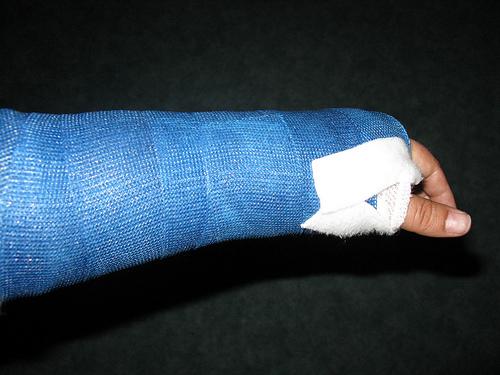

Arm Gebrochen, Wie Langer Dauert Der Heilungsprozess (Unfall, Heilung

gebrochen gips heilungsprozess dauert unfall dauer heilung.

gebrochen röntgenbild dauert heilungsprozess seesaw gutefrage heilung unfall dauer.